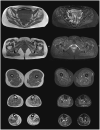

Mutations in the MATR3 gene are associated to distal myopathy with vocal cord and pharyngeal weakness (VCPDM), as well as familiar and sporadic motor neuron disease. To date, 12 VCPDM families from the United States, Germany, Japan, Bulgary, and France have been described in the literature. Here we report an Italian family with a propositus of a 40-year-old woman presenting progressive bilateral foot drop, rhinolalia, and distal muscular atrophy, without clinical signs of motor neuron affection. Her father, deceased some years before, presented a similar distal myopathy phenotype, while her 20-year-old son is asymptomatic. Myopathic changes with vacuolization were observed in muscle biopsy from the propositus. These results, together with the peculiar clinical picture, lead to MATR3 gene sequencing, which revealed a heterozygous p.S85C mutation in the propositus. The same mutation was found in her son. Over a 5-year follow-up, progression is mild in the propositus, while her son remains asymptomatic. Clinical, radiological, and pathological data of our propositus are presented and compared to previously reported cases of VCPDM. VCPDM turns out to be a quite homogenous phenotype of late-onset myopathy associated to p.S85C mutation in MATR3 gene. MATR3-related pathology, encompassing myopathy and motor neuron disease, represents an illustrative example of multisystem proteinopathy (MSP), such as other diseases associated to mutations in VCP, HNRNPA2B1, HNRNPA1, and SQSTM1 genes. The present report contributes to a further characterization of this still poorly understood pathology and points out the diagnostic utility of muscle biopsy in challenging cases.